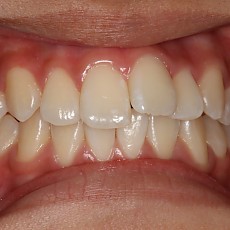

시술전후사진 6 페이지

Total 189건 6 페이지